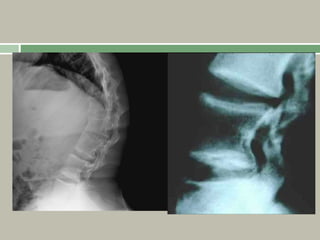

Odontoid hypoplasia together with the ligamentous

laxity can result in cervical atlantoaxial instability

(AAI), which can cause symptoms ranging from

increased fatigability to myelopathy.

Radiographic investigations for C1–2 instability are

therefore necessary in the pre-operative assessment of

Spine

Platyspondyly, with anterior beaking and irregular

endplates,

Normal interpedicular distance

Odontoid hypoplasia

Atlantoaxial instability may be seen on flexion or

extension views.